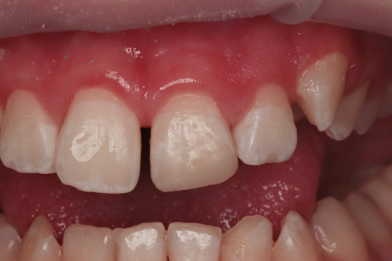

«Реставрация 1.1,2.1 зуба после ортодонтического лечения» доктора: врач - ортодонт Таранова К.С. ; врач- терапевт Рахманова М.А.

Рахманова Марина Александровна -